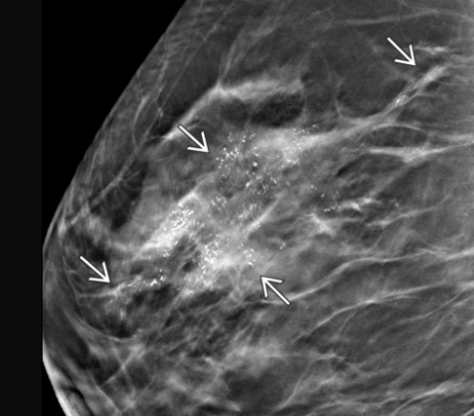

typically benign calcifications

BI-RADS for new or changing calcs

4 or 5

anything new or changing is suspicious!